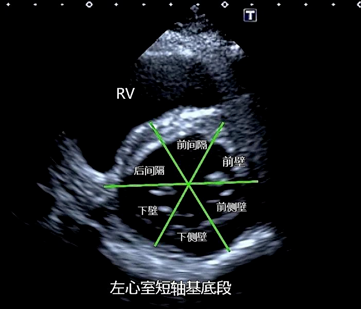

在短轴切面上,将基底环和中间环分为六个区域(每个区域占左心室周长的60°),将心尖环水平分为四个区域(每个区域占该水平的左心车周长的90°),区域的分割开始于室间隔和石心室游离壁的前交界处并逆时针旋转,这样就形成了16个节段,分别为:

基底环:(1)前间隔基底段(2)后间隔基底段(3)前壁基底段、(4)下壁基底段(5) 前侧壁基底段 (6)下侧壁基底段